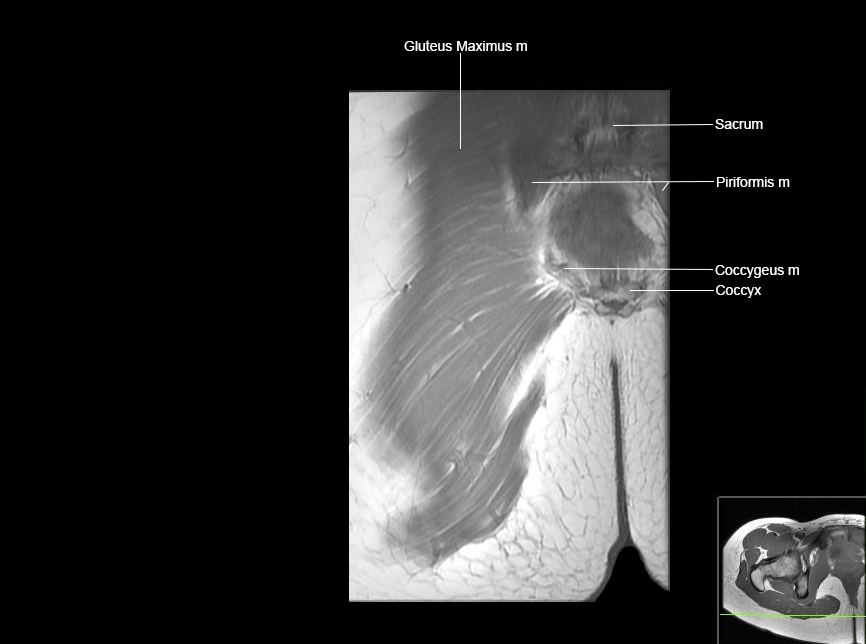

MRI Hip Anatomy

Scroll using the mouse wheel or the arrows